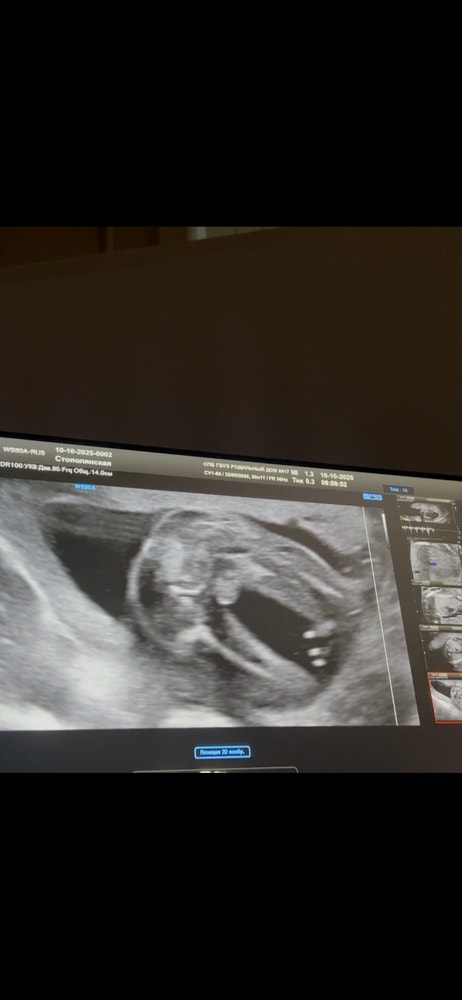

Кто на узи?

Анализы, скринингиНа 2х скринингах сказали что девочка, не верю, сняла видео ставлю на паузу и вижу яцйца.

На 21 неделе беременности яйца, как вы выразились, находятся внутри брюшной полости, то, что вы видите- это большие половые губы либо мошонка, на таком снимке не определишь точно, так как не видна область срединного шва. Но отсутствие пениса намекает, что это таки половые губы.

Мне кажется, что тут однозначно мальчик.

Хотя у меня с первой дочерью был похожий кадр, но это только на одно аппарате УЗИ, возможно врач как-то не так навела и от чего-то легла тень удачно)

На фото больше похоже на мальчика,но как-то сложно поверить,что врачи на втором скрининге могут ошибаться. Сдайте кровь на определение пола,это будет куда быстрее чем третий скрининг.